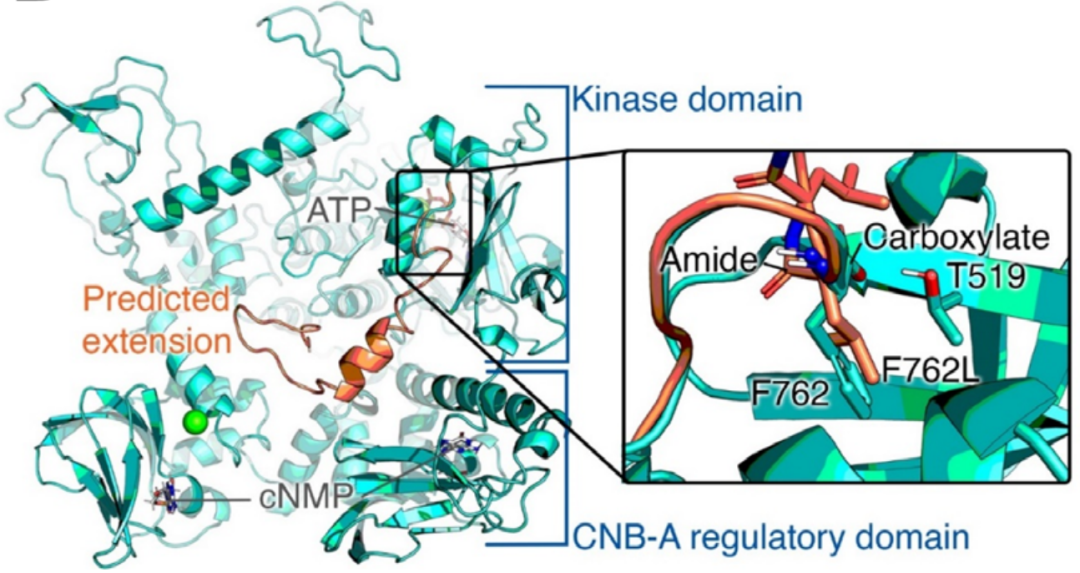

这里描述的这两种变异都非常罕见,gnomAD数据库中没有p.Asp761Glufs*34,而p.Arg569*为单基因。在这两个家系中,致病变异都存在于较大的ROHs中。虽然p.Arg569*突变已经被证明影响下游的MAPK途径,但家系1中的p.Asp761Glufs*34很可能也是有害的,因为蛋白C末端Asp>Phe及33个氨基酸发生替换。在计算机建模中的研究突出了该区域的结构重要性,特别是终末Phe762残基。

cGKII (野生型: 绿松石色)的结构,与突变体 (橙色,762突变且多出一段)